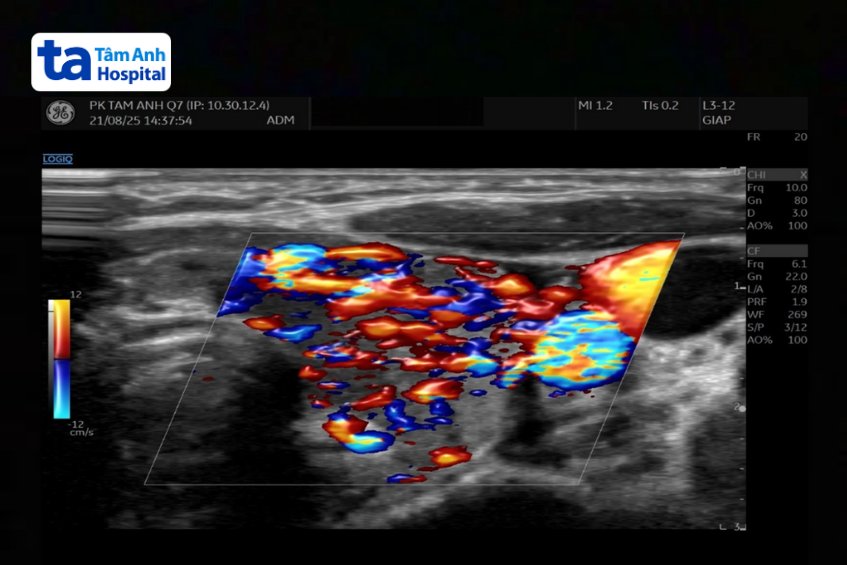

Kết quả xét nghiệm cho thấy nồng độ thyroxine tự do FT4 của bé lên đến 47.64 pmol/L (bình thường dưới 20). Hormone kích thích tuyến giáp TSH giảm còn 0.005 uU/mL (bình thường 0.34 – 5.6), tức gần như bị ức chế hoàn toàn, cho thấy tuyến yên đã ngừng kích thích tuyến giáp do nồng độ hormone giáp trong máu tăng cao. Bác sĩ chẩn đoán bé bị cường giáp do bệnh Basedow (Graves) – một bệnh lý tự miễn khiến cơ thể sản sinh kháng thể kích thích tuyến giáp hoạt động quá mức.